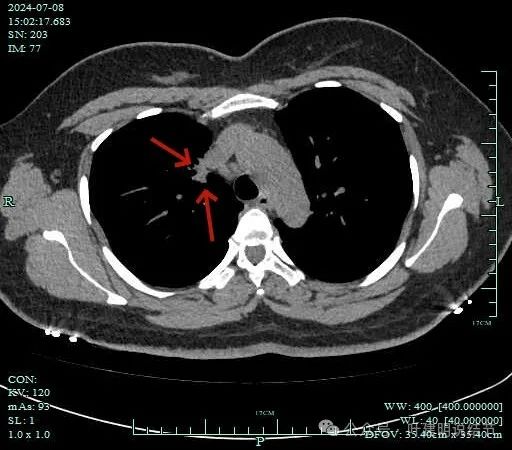

再看2024年7月份的影像:

病灶纵隔窗上是软组织影,表面不平,形态不规则。上腔静脉旁有肿大淋巴结。

病灶膨胀性不明显。

邻近支气管有扩张,表面不平,分叶明显。